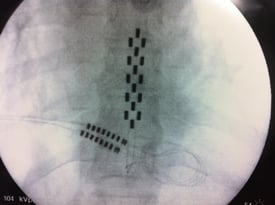

Phase de test avec une électrode chirurgicale pour soulager des douleurs chroniques post-chirurgicales

Electrode per-cutanée visant à soulager des douleurs chroniques post-chirurgicales